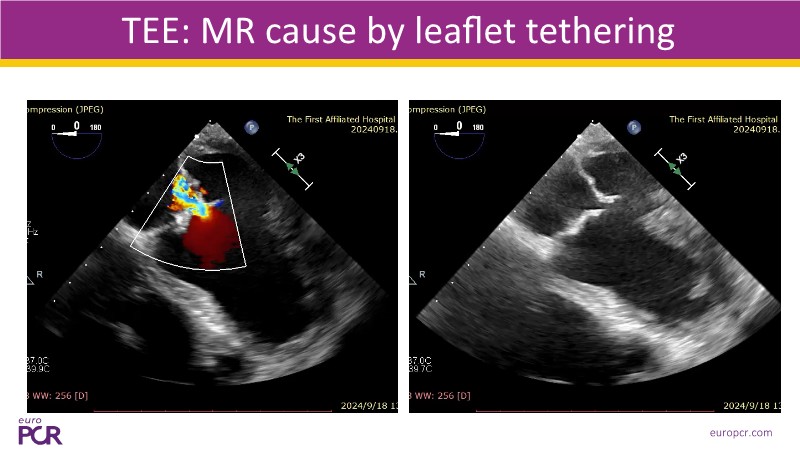

- To discover tips and techniques for mitral TEER in patients with challenging anatomy and difficult imaging